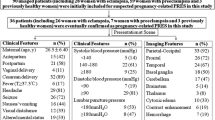

Table 1 summarizes the demographic information and clinical presentation of all patients. In patients with more than one factor that may have led to PRES, we used the patient’s clinical presentation to determine which factor was most relevant.

Of 30 patients with PRES, 24 patients (80%) had systemic hypertension at the time of the acute event. The most common associated condition in patients with PRES and systemic hypertension was preeclampsia–eclampsia (n = 10), followed by patients suffering from acute or chronic renal failure (n = 6), and patients receiving chemotherapeutic and immunosuppressant agents [cyclophosphamide (n = 2), cyclosporine A (n = 2), tacrolimus/FK-506 (n = 1)]; one patient developed PRES during an allergic shock after intake of strawberries and nuts; in two patients, PRES occurred during a hypertensive crisis after multi-drug abuse and 1 day after surgery for an ovarian carcinoma, respectively;

In six of 30 patients (20%), the systemic blood pressure level when PRES occurred was within normal limits. Three of six patients with PRES and normal BP were receiving immunosuppressive agents, such as tacrolimus/FK-506 (n = 2) and cyclosporine A (n = 1). One patient with PRES received high dose cyclophosphamide for treatment of systemic lupus erythematosus. Two patients with normotensive PRES developed symptoms during chemotherapy for treatment of pancreatic carcinoma (gemcitabine and oxaliplatin, #18) and multiple myeloma (Velcade®, generic name: Bortezomib, #15), respectively.

In one patient with PRES and tacrolimus/FK-506 therapy, the drug blood level was potentially toxic (#9); in all other patients with PRES and immunosuppressive drug therapy or chemotherapy, drug levels were within the therapeutic range at presentation.

Two patients died 8 and 6 weeks after the acute event due to thromboembolic brain infarctions (#20) and multi-organ failure (#8), respectively. Six patients (#13, #14, #15, #28, #29, and #30) had residual symptoms at hospital dismissal, such as extremity weakness and confusion. The remaining patients were discharged without residual neurological symptoms.

No significant differences were seen in LDH levels (hypertensive patients: mean 393.83 ± 227.66 U/l; normotensive patients: mean 389.5 ± 152.62; normal range <248; Mann–Whitney U test, p = 0.77) or creatinine levels (hypertensive patients: mean 2.29 ± 2.36 mg/dl; normotensive patients: mean 2.44 ± 2.06 mg/dl; Mann–Whitney U test, p = 0.454) between patients with normotensive and hypertensive PRES.

Lesion distribution

Statistical evaluation did not reveal any significant difference between the normotensive and hypertensive patient groups with regard to the location of affected brain regions; the occipital lobes were the most commonly affected brain region in both the hypertensive and the normotensive patient groups and were involved in all but two patients (93%). The second most commonly affected brain regions were the frontal lobes and the cerebellum in 16 (53%) and 13 patients (43%), respectively. The parietal lobes were affected in 12 (40%), and the temporal lobes in ten patients (33%). The pons was affected in nine patients (30%), three of whom suffered from preeclampsia–eclampsia. The basal ganglia were exclusively affected in patients with elevated blood pressure levels (n = 9; 30%) and six of whom suffered from preeclampsia–eclampsia. There was a tendency toward involvement of the basal ganglia in patients with preeclampsia–eclampsia compared to patients without preeclampsia–eclampsia (Mann–Whitney U test, p = 0.066). Basal ganglia involvement, at least unilateral, was apparent in 60% of patients with preeclampsia–eclampsia compared to 18.2% in non-eclamptic patients. Of seven patients with lesions in the thalamic regions, four were suffering from preeclampsia–eclampsia and, in five of seven patients with thalamic involvement, the basal ganglia were affected simultaneously. The corpus callosum was affected in four patients, two of whom had normal blood pressure levels.

Extent of edema and number of affected brain regions

There was no statistically significant difference between the extent of edema in the various brain regions in patients with hypertension compared to patients without hypertension. When patients with or without preeclampsia–eclampsia were compared, there was also no statistically significant difference with regard to disease severity.

In all but three patients, more than one brain region was involved (Fig. 4). With regard to the number of affected brain regions, there was a significant difference between patients with and without preeclampsia–eclampsia. The mean number of affected brain regions in patients with preeclampsia–eclampsia was 4.9 ± 1.66 compared to 3.74 ± 1.84 brain regions in patients without preeclampsia–eclampsia (Mann–Whitney U test, p = 0.046).